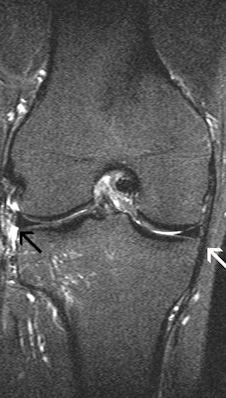

These images show the three most common knee injuries. Left: Osteoarthritis. On the x-ray, the osteoarthritis is clearly recognizable, with the narrowed joint space. Right: Lateral ligament tear. MRI shows the torn lateral ligament (black arrow). The medial ligament (white arrow) is still intact. Copyright of all images: Universitätsklinikum Essen.